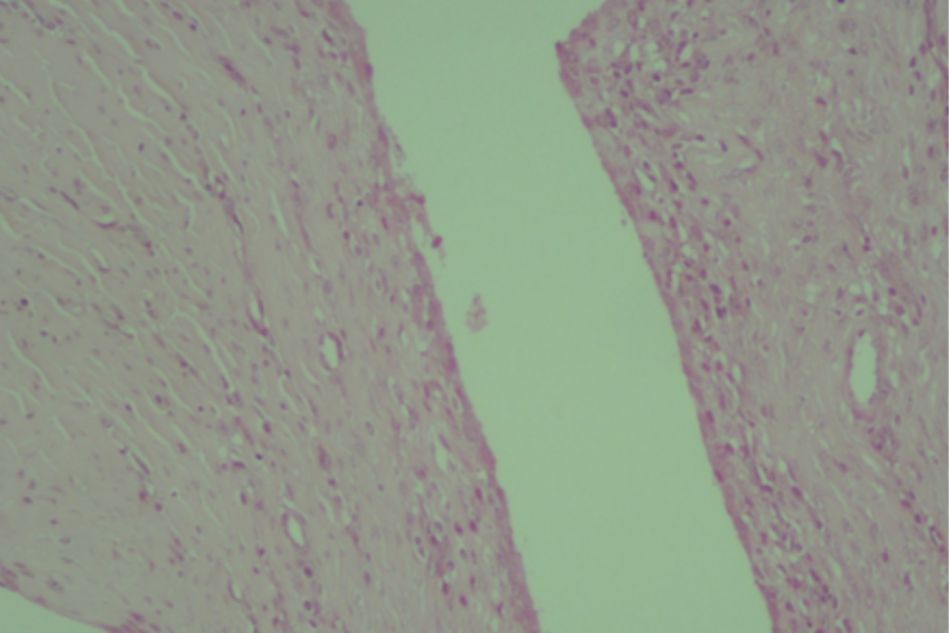

Figure 2.7. Knee joint sample in Group IV (rat no.41)

Mild subchondral bone and cartilage damage

Figure 2.8. Knee joint sample in Group IV (rat no.42)